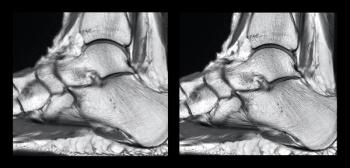

UTE-MRI can be a valuable alternative in situations where repeated radiation exposure is of concern.